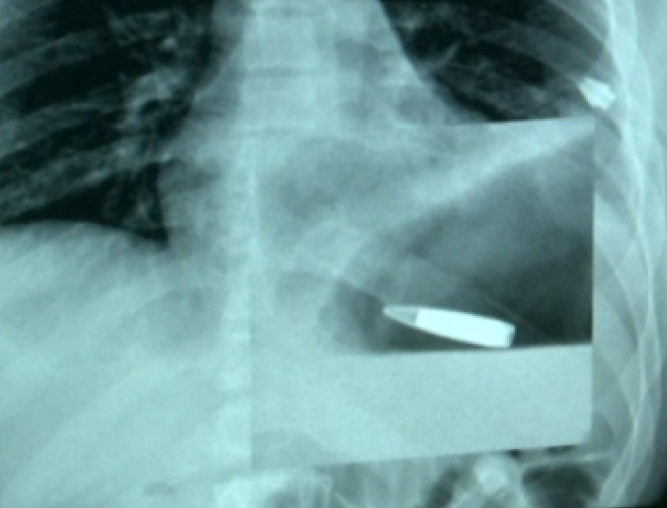

Зазначається, що пристрій ефективно видаляє уламки куль і снарядів з феромагнітними властивостями, що глибоко проникли в м’які тканини організму.